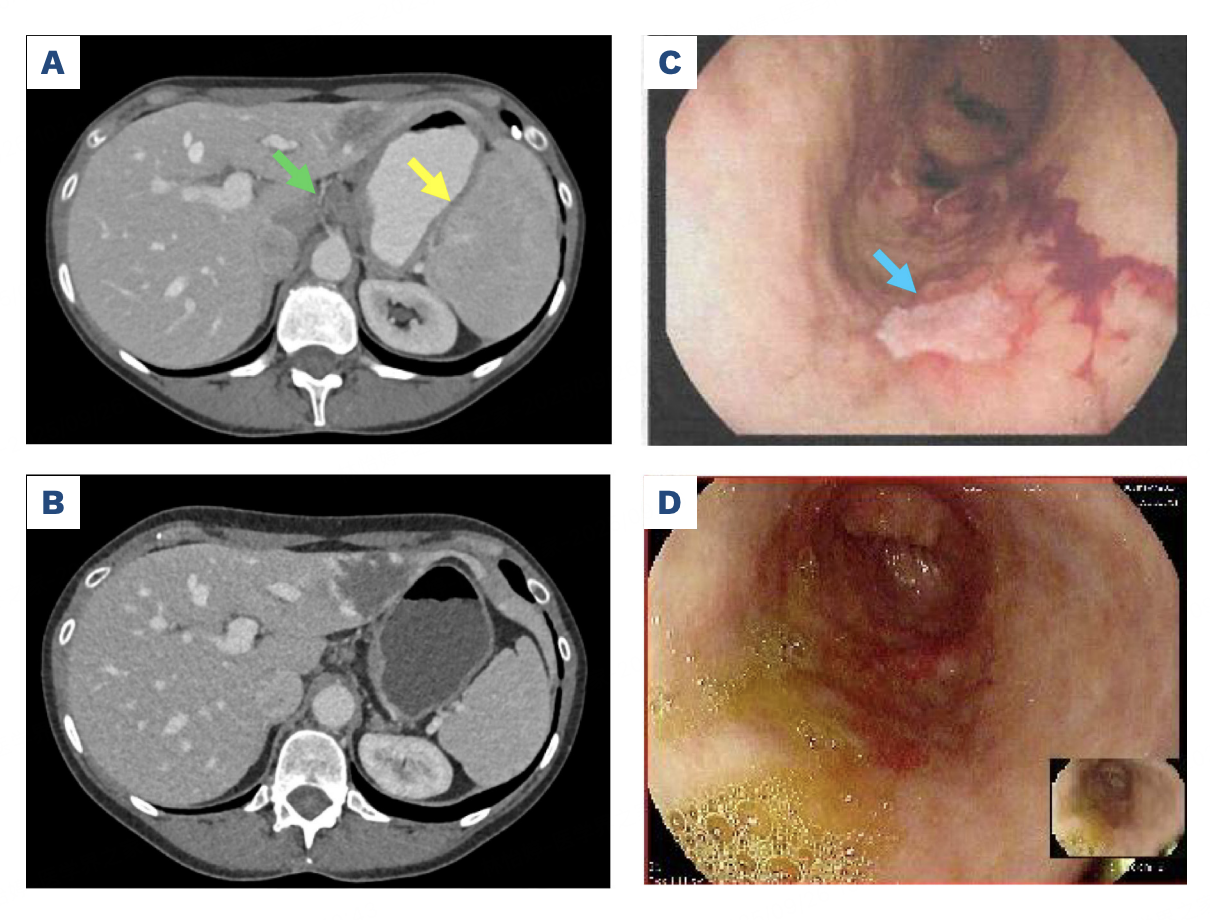

Odronextamab治疗带来了惊人的效果:治疗12周后,PET-CT、胃镜活检及骨髓穿刺均证实淋巴瘤病灶完全消失(CR);更关键的是,血清总IgM水平和致病的抗H因子IgM抗体被完全清除。由于病源被根除,医生在密切监测下成功停止了依库珠单抗的治疗,在长达8个月的随访中,患者的aHUS未再复发(图1)。

图1.Odronextamab治疗前后的腹部计算机断层扫描与胃镜检查结果。(A) Odronextamab治疗前实施的增强腹部CT扫描图像。绿色箭头指示腹腔干三支动脉旁淋巴结肿大,黄色箭头显示中度脾肿大。(B) 经Odronextamab治疗三个月后的增强腹部CT扫描,显示腹腔干三支动脉旁淋巴结肿大及脾肿大均已消退。(C) 治疗前胃镜检查图像,蓝色箭头标示一处纤维蛋白渗出性溃疡,该部位胃组织活检证实存在边缘区淋巴瘤浸润。(D) Odronextamab治疗三个月后胃镜检查显示溃疡已完全消退。